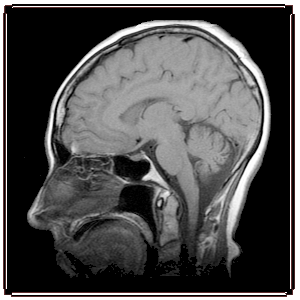

Oxidative Stress and Its

Functional Consequences Measured

In Vivo  Using MRI

Dr. Berkowitz' research focuses on transformational  in vivo  MRI evaluation of oxidative stress in emerging diseases such as neurodegeneration -- without the need to inject a contrast agent to determine how and when antioxidant treatment efficacy is best achieved.

This new ability enables earlier evaluation of disease progression and anti-oxidant treatment efficacy than is currently possible with conventional methods. Most of Dr. Berkowitz' new assays of excessive free radical production and function are based on endogenous contrast mechanisms, which will greatly facilitate their translation into patients.